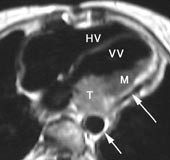

Ved høyre ventrikkel-dysplasi – en arvelig sykdom som kan gi alvorlige rytmeforstyrrelser – sees varierende grader av fettinfiltrasjon i myokard. Spesielt utsatt er høyre ventrikkels frie vegg (fig 8). T1-vektede bilder viser tydelig forskjell på fettvev (hvitt) og myokard (mellomgrått) og er den bildediagnostiske metoden som er best egnet til å vise fettinfiltrasjonen (19). Tilstanden kan også ytre seg som regional eller generell fortynning av høyre ventrikkels frie vegg. De patologiske områdene er ofte hypokinetiske, hvilket kan fremstilles med cine-MR.

T1-vektede MR-bilder viser det normale perikard som en mørk stripe mellom to lyse vev, det epikardiale fettvev og det perikardiale fettvev (fig 8, 9). Fortykkelse av perikard ( ≥ 4 mm) kan av og til sees ved akutt perikarditt, men er mer vanlig ved kronisk perikarditt. MR er en sensitiv metode til å påvise konstriktiv perikarditt (20). I tillegg til perikardfortykkelsen, sees dilatasjon av høyre atrium, v. cava inferior og levervenene og normalt stor eller liten høyre ventrikkel. MR er imidlertid en dårlig metode til å påvise forkalkninger i perikard. Perikardvæske har et varierende utseende ved MR avhengig av innhold av protein og andre makromolekyler. Stormolekylære stoffer forkorter væskens T1 og forårsaker økt signalstyrke på T1-vektede bilder. Eksudatet i perikard ved den sterkt inflammatoriske uremiske perikarditt gir således et moderat kraftig signal på T1-vektede bilder, mens det perikardiale transsudat som sees ved f.eks. hjertesvikt, har nesten manglende signal på T1-vektede bilder (fig 7). Hemoperikardium har et karakteristisk utseende med en intens signalstyrke på T1-vektede bilder.